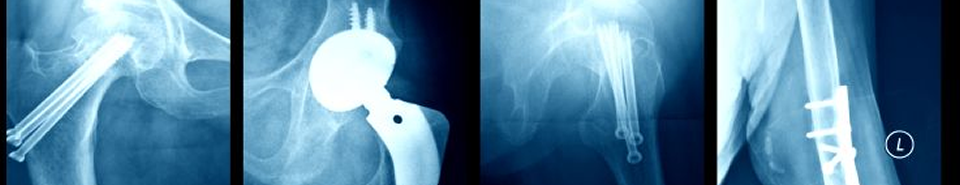

Each year medical device makers offer for sale and use hundreds of medical devices designed to be implanted in the human body. These devices include joint replacement implants, such as knees, hips and other joints; bone stabilization implants, such as plates, rods, pins and screws; synthetic surgical mesh, such as transvaginal mesh, transabdominal mesh and mesh slings; cosmetic implants, such as facial implants, dental implants and breast implants; and other surgical instruments, devices and monitors. Improperly designed or tested medical implants can and often do cause serious injuries and even death.

Before a medical implant, such as an artificial hip or knee or cardiac pacemaker, can be sold in the United States, the manufacturer must put the device through testing and trials. The manufacturer then must submit the implant to the Food and Drug Administration (FDA) for approval before the device can be distributed in the United States. Due to its limited resources, the FDA is unable to carefully test and screen all such devices or surgical tools. Sometimes, the FDA approves a new device or implant on the basis of its "substantial similarity" to an already existing device. Unfortunately, this can and has led to instances where a device has been approved and it is later discovered that the device is defective as failures occur after the device or implant has been placed in patients.

Hip Implants

• Biomet M2a-Magnum Hip Replacements

• DePuy Hip Replacements

• Stryker® Rejuvenate Hip Implant

• Wright Medical Technology Hip Replacements

• Zimmer Durom® Cup Hip Replacement

Ken Hooks has extensive experience investigating and pursuing claims involving defective medical devices, equipment and implants. In a meritorious case, you may be entitled to monetary damages for past and future medical expenses, lost earnings, pain and mental anguish. In certain cases, you may also be entitled to medical monitoring and punitive damages. If you or a loved one suffered a serious injury or death as the result of a defective medical implant, please contact us for a confidential, no-cost, no-obligation consultation.